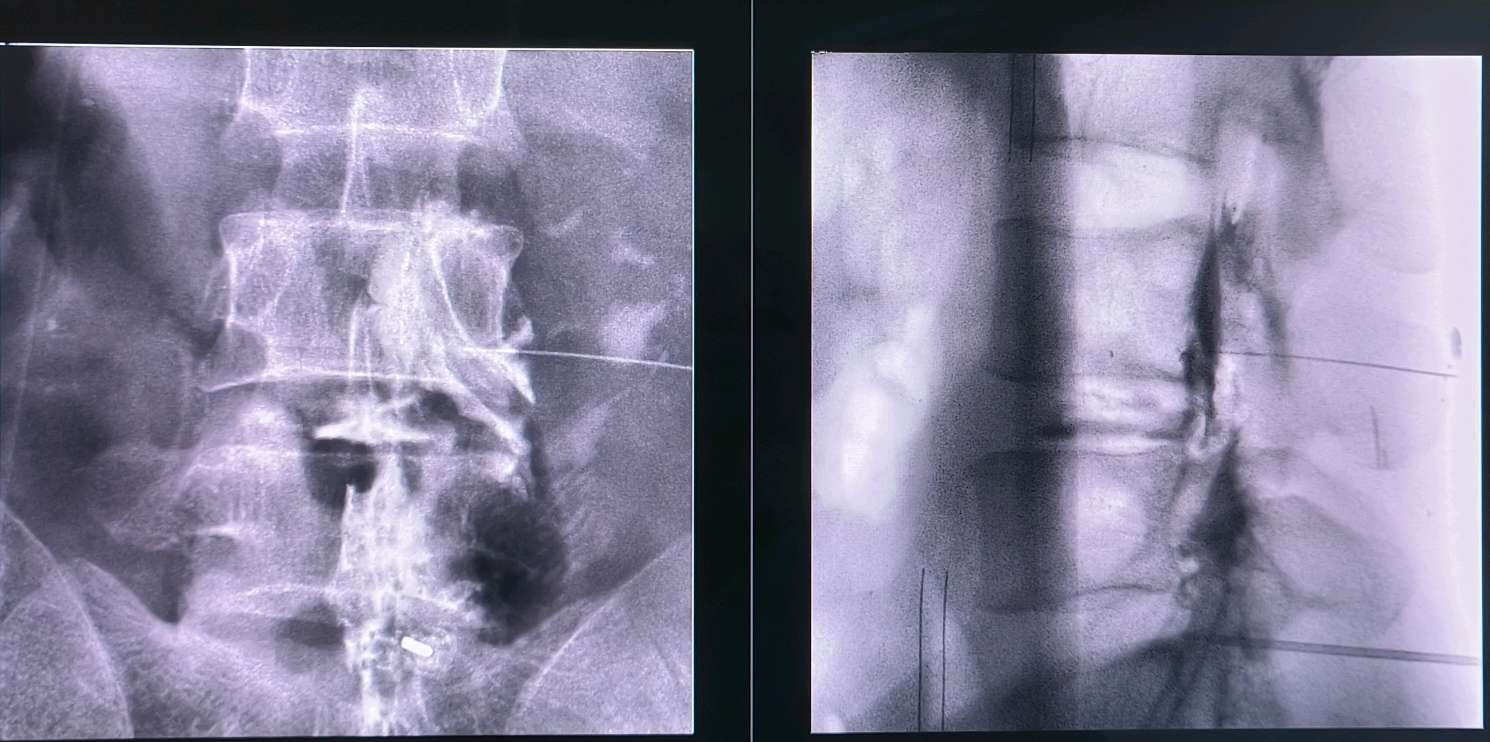

有,胶原酶技术是个古老而又新兴的技术,胶原酶可以水解突出的椎间盘,变成水和氨基酸,更绿色,更微创,无痛苦,可以说是一根针一个针眼解决椎间盘突出

问题,不开刀,临床疗效不差于开放手术!